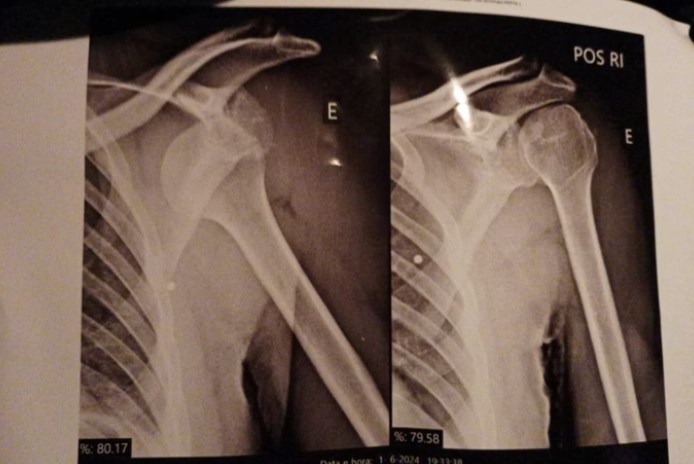

Outro ponto denunciado por Lucas é a dificuldade de atendimento no Hospital da Polícia Militar (HPM). Ele sofreu duas luxações nos ombros, foi socorrido por viaturas da própria PM, mas precisou esperar horas por atendimento, sem conseguir consulta com ortopedista.

Diante da demora, buscou atendimento no Hospital do Tatuapé, referência em traumas ortopédicos pelo SUS. Lá, foi operado em janeiro deste ano. Mesmo assim, os atestados emitidos pela unidade de saúde pública precisavam ser validados pelo setor médico da PM, que frequentemente reduzia o período de afastamento.

“Na primeira luxação, o médico do SUS recomendou três meses de repouso. A PM autorizou apenas um. Nesse período, tive novos episódios e precisei de novos afastamentos. Eles só prorrogavam porque o ombro voltava a sair do lugar, não por prevenção, mas por necessidade”, explicou.

Lucas relata que hoje até tarefas simples, como vestir uma camisa, se tornaram um desafio. O ombro esquerdo já foi operado, mas ele ainda sente dores e precisa de fisioterapia. O direito também deverá passar por cirurgia.